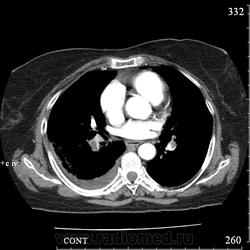

Еще один случай диагностики ТЭЛА методом КТ-ангиографии у женщины 59 лет. Основная клиническая жалоба - выраженная одышка. Определяется: полный дефект наполнения в системе правой ЛА (бифукация и нижнедолевая), неполный дефект наполнения в левой ЛА (нижнедолевая), пристеночные тромбы по задней стенке в области бифуркации обеих легочных артерий. Инфаркт (массивное кровоизлияние) нижней доли правого легкого. Правосторонний малый (120см3) гидроторакс. Несмотря на выраженные тромбы, поперечники легочных артерий - в пределах нормы.; на нативной (безконтрастной) КТ - тромбы не видны. Несмотря на почти полный дефект наполнения в левой нижнедолевой артерии, изменений в легочной ткани левого легкого нет. Также приводится топограмма, как вариант, приближенный к рутинной рентгенограмме

В данном случае не просто КТ, КТ-ангиография - сила. Нативное КТ, также не ответило бы на все вопросы.

Как бы тромб-наездник, окклюзия справа выраженная, но и слева имеется.